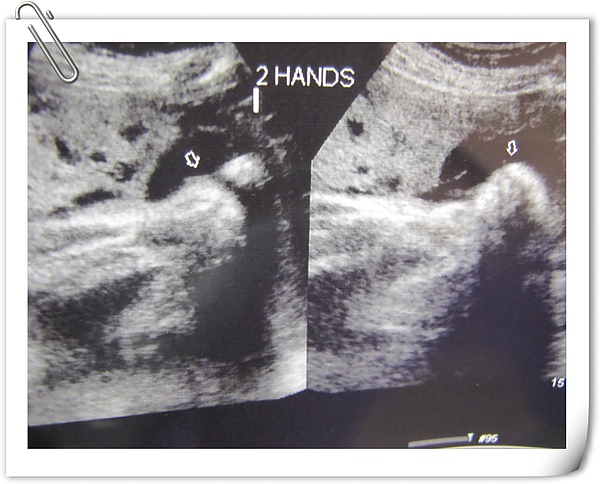

不過二隻手一直緊握拳頭,應該是害羞吧~~

終於把手手打開,也是正常的五根,右邊那張只有四根,因為大姆指被含在小嘴裡